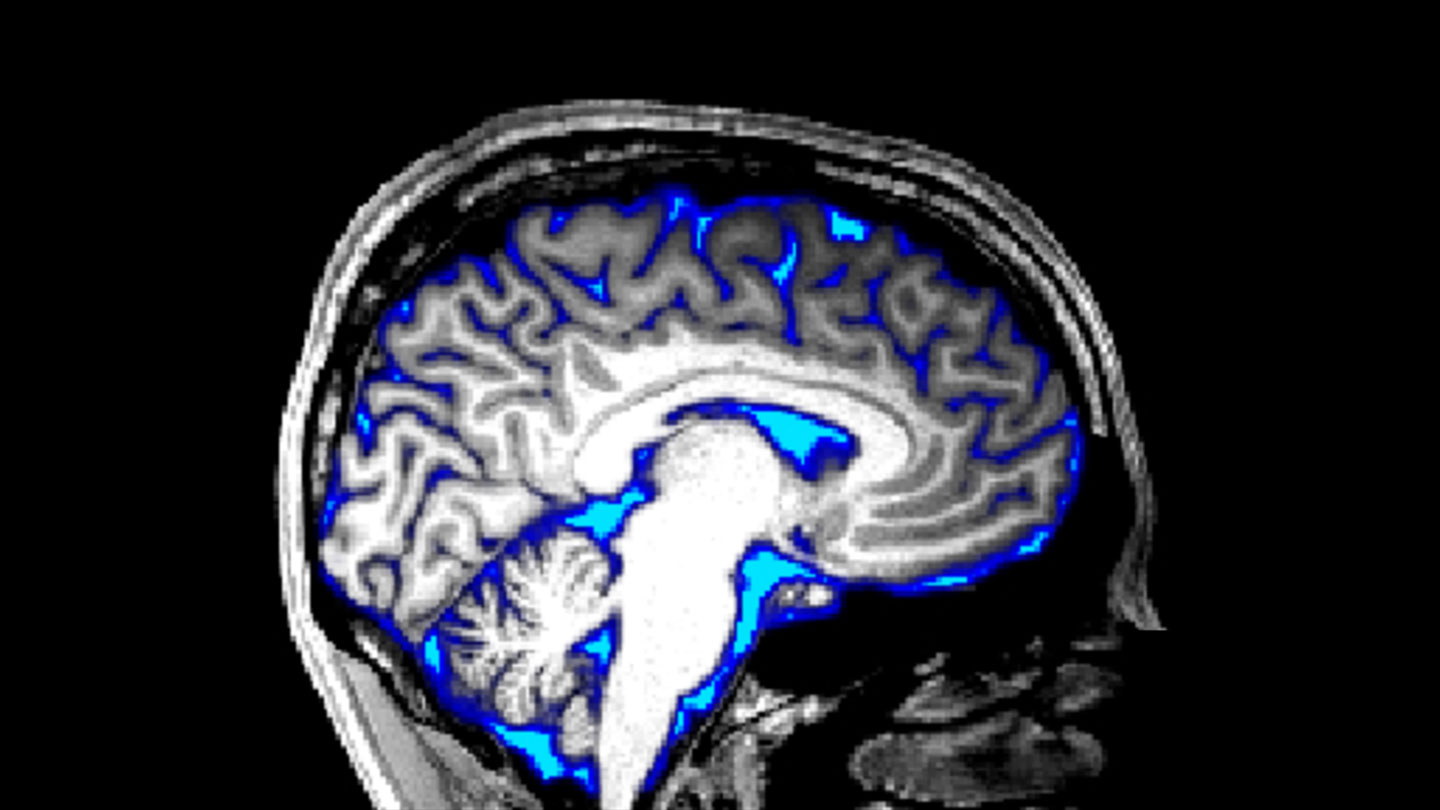

Background: Immune modulation may improve outcome in HIV-associated cryptococcal meningitis. Animal studies suggest alternatively activated macrophages are detrimental but human studies are limited. We performed a detailed assessment of the cerebrospinal fluid (CSF) immune response and examined immune correlates of disease severity and poor outcome, and the effects of antiretroviral therapy (ART).

Methodology: We enrolled persons ≥18 years with first episode of HIV-associated cryptococcal meningitis. CSF immune response was assessed using flow cytometry and multiplex cytokine analysis. Principal component analysis was used to examine relationships between immune response, fungal burden, intracranial pressure and mortality, and the effects of recent ART initiation (<12 weeks).